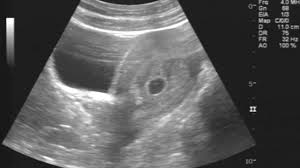

또 하나 팁을 드리자면, 임신 초기 증상을 느꼈을 땐 조급하게 임신테스트기를 사용하기보단, 생리 예정일로부터 최소 2~3일 후에 테스트를 권장드려요. 너무 빨리하면 정확한 결과가 안 나올 수 있어요. 그리고 가장 확실한 건 산부인과에서 혈액검사나 초음파 검사를 통해 확인하는 것이고요.